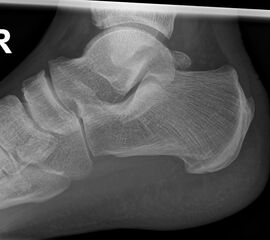

Fersenbein lateral

Positionierung:

• Patient in Seitenlage.

• Fuß mit der Außenseite aufliegend.

• Ferse liegt parallel zum Tisch.

• Röntgenröhre 90° zur Senkrechten.

• Zentralstrahl von lateral nach medial, zentriert auf das Fersenbein ca. 1-2 Querfinger distal der Malleolen.

Kennzeichen des Röntgenbildes:

• Seitliche Darstellung des Fersenbeins mit scharfen Knochenkonturen.

• Gut einsehbares unteres Sprunggelenk (Articulatio talocalcaneonaviculare).

• Gut einsehbares Gelenk zwischen Calcaneus und Os cuboideum.

Besondere Bemerkungen zum Beispielbild:

• Darstellung der Kalkaneus seitlich.

• Kleiner Traktionssporn im Insertionsbereich der Achillessehne.

• Großes Os trigonum dorsal des Talus.